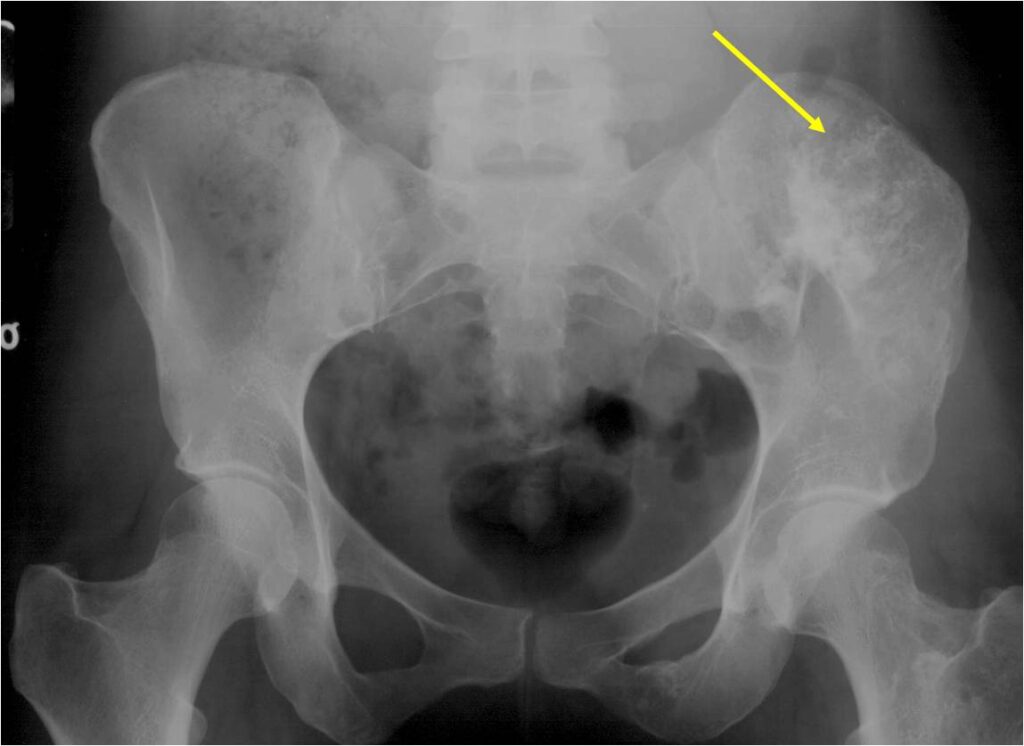

- Enchondromas of the pelvis, vertebrae and ribs are uncommon

- Almost all hyaline cartilage tumors of the pelvis are considered malignant based on anatomic location no matter what the pathology shows. These tumors will ultimately grow locally and have the potential to dedifferentiate or change into a higher grade chondrosarcoma.

Radiographic Presentation

- Localized, radiolucent defect usually with punctate calcifications

- Calcifications are typical but not always present

- Matrix may demonstrate various degrees of calcification

- Calcifications are stippled, punctate, popcorn like calcifications and “Ring and Arc” calcifications

- Cartilage tumors grow in a lobular manner. The perimeters of the lobules undergo

- enchondral ossification that may calcify. If the entire perimeter of the lobule calcifies it appears

- radiographically as a “Ring”. If a portion of the perimeter of a lobule calcifies it forms an “Arc” on

- an X-ray.

Plain X-Ray:

- Geographic lytic lesion

- Central often metaphyseal in long bones

- Can be eccentric also

- Expansile remodeling with thinned cortex

- Chondroid matrix with calcifications in majority of tumors

- Approximately 20% have limited or no calcifications

Ring and Arc Calcifications Minimal Endosteal Scalloping Cortex Intact No Soft Tissue Component No Periosteal Reaction

Ring and Arc Calcification No Endosteal Scalloping

Metaphyseal Tumor Heavy Calcifications Ring and Arc Pattern of Calcifications Minimal Endosteal Scalloping No Cortical Destruction No Periosteal Reaction No Cortical Destruction No Soft Tissue Component